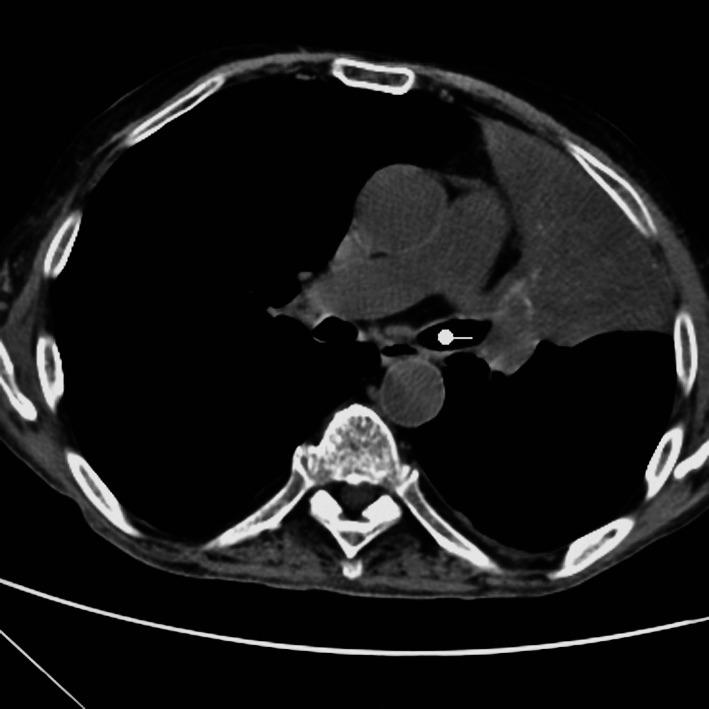

The objective is to present diagnostic capabilities of virtual bronchoscopy (VB) and fiberoptic bronchoscopy (FB) for determining the localization and shape of stenoses in patients with central lung carcinoma. A systematic study was performed on 220 patients aged 11-83 (54.36±17.24) years with endobronchial disease using the FB and VB methods during the 2013-2017 period. Central carcinoma of the lung was found on VB in 130 patients and on FB in 120 patients. Other nosologic diseases were found in 22 patients. Right localization of central carcinoma prevailed over left localization in both sexes. A significant difference in the localization criterion was found in female patients examined by VB (U-test, p=0.01). VB and FB yielded 86.5% . 91.60% precision and 85% . 94.5% sensitivity. In conclusion, VB was found to be a successful noninvasive method for determining the localization of lung tumors and shape of stenoses, which are essential in the diagnosis of malignant processes.

目的是展示虚拟支气管镜(VB)和纤维支气管镜(FB)在确定中央型肺癌患者狭窄的定位和形态方面的诊断能力。在 2013-2017 年期间,对 220 名年龄在 11-83 岁(54.36±17.24)岁的患有支气管内疾病的患者使用 FB 和 VB 方法进行了系统研究。在 130 名患者中通过 VB 发现中央型肺癌,在 120 名患者中通过 FB 发现中央型肺癌。在 22 名患者中发现了其他疾病。在男女患者中,中央型肺癌的右定位均超过左定位。在通过 VB 检查的女性患者中,定位标准存在显著差异(U 检验,p=0.01)。VB 和 FB 的精确率分别为 86.5%和 91.60%,灵敏度分别为 85%和 94.5%。总之,VB 被发现是一种成功的非侵入性方法,可用于确定肺部肿瘤的定位和狭窄的形态,这对于恶性过程的诊断至关重要。